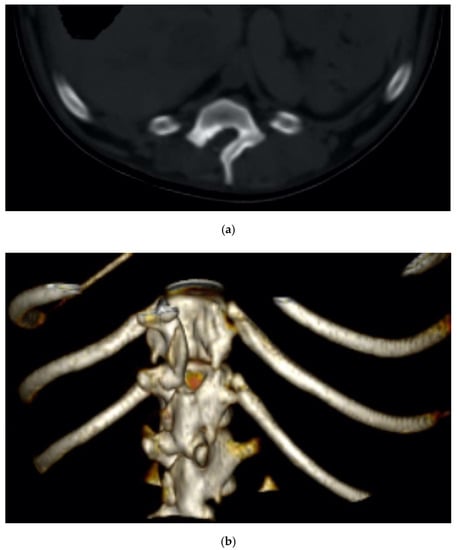

The minimal invasiveness of the piezo cut was also confirmed by the imaging follow-up, where the incidence of the osteosclerosis and bone resorption at the osteotomized surfaces was negligible (Figure 9a,b).

Figure 9.

Two-dimensional (a) and 3D (b) CT scan of an explicative case of dorsal hemilaminectomy performed in a dachshund diagnosed with a spinal cord compression.